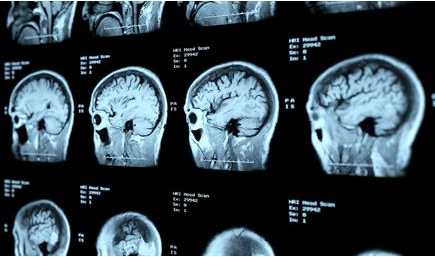

A stroke is a medical emergency that occurs when the blood supply to your brain is cut-off or severely reduced. Prompt treatment is required to minimize brain damage and prevent further complications.

There are two main types of strokes; ischemic and hemorrhagic.

Ischemic strokes are caused by a blood clot blocking the blood flow through the arteries supplying your brain. Brain tissue that doesn’t receive sufficient oxygen cannot survive and begins to die, causing recognizable symptoms. Blood clots commonly occur due to atherosclerosis, which is a build-up of fatty deposits in your arteries. Alternatively, they may form in the heart and from there may travel and lodge in a blood vessel in the brain.

Less commonly, hemorrhagic strokes can happen due to a leak or rupture in one of the blood vessels in the brain. This causes a collection of blood in the substance of the brain which results in local damage.